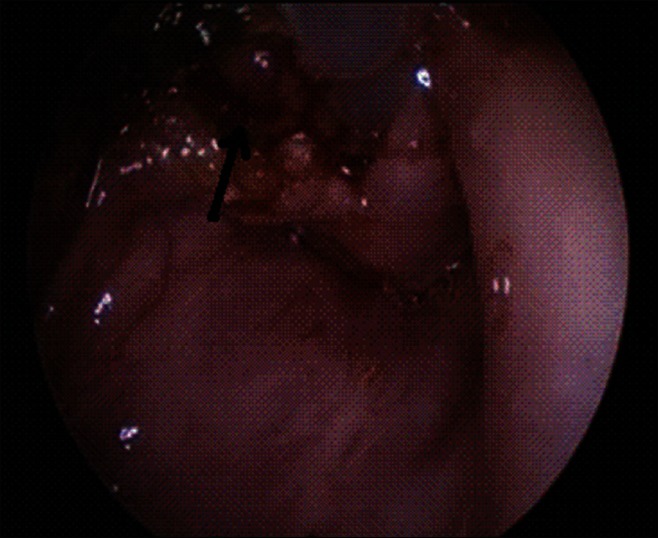

Vallecular cyst is a rare cause of upper airway obstruction in infants and children and presentation like acute stridor with near fatal respiratory distress is extremely rare. It is one of the rare causes of difficult intubation, during which cyst aspiration can improve the access. Vallecular cyst is commonly managed using microlaryngoscope and specialized instruments. We hereby report a method of endoscopic management of these cysts using conventional laparoscopic instruments.

Abstract Image